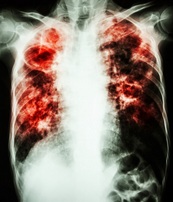

Справка. Туберкулез - инфекционное заболевание, передающееся воздушно-капельным путем. Без соответствующего лечения человек, больной активной формой туберкулеза, ежегодно может заразить 10-15 человек. По данным ВОЗ, каждый день от этой предотвратимой и излечимой болезни умирает почти 4 400 человек, а почти 30 000 человек заболевают ею (большинство из которых - жители развивающихся стран).

Туберкулез по-прежнему является ведущей причиной смертности от инфекционных болезней в мире. Развитию туберкулеза способствует неполноценное питание, потребление токсических продуктов (табак, алкоголь, наркотики), неудовлетворительные условия труда и быта, хронические заболевания (сахарный диабет, заболевания крови, ВИЧ).